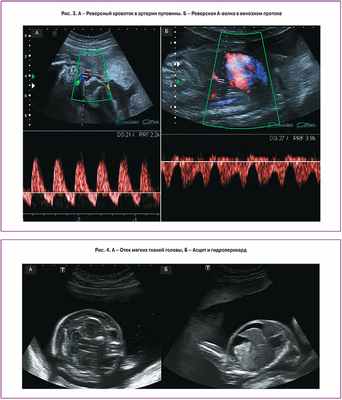

III стадия характеризуется нарушением кровотока одного или обоих плодов. При допплеровском исследовании кровотока в артериях пуповины выявляются нулевой или реверсный диастолический компонент, реверсная А-волна в венозном протоке или пульсирующий спектр в вене пуповины (рис. 3). Таким образом, возможны различные комбинации нарушений кровотока, выявляемые при допплерометрии. Как правило, нарушения кровотока в артериях пуповины чаще выявляются у донора, в то время как у реципиента чаще диагностируют аномальный кровоток в венозном протоке или пульсирующий спектр в вене пуповины, что свидетельствует о развивающейся сердечной недостаточности.

При IV стадии ФФТС у одного из плодов, чаще у реципиента, возникает водянка (асцит, гидроперикард, плевральный выпот и отек подкожно-жировой клетчатки головы и туловища) (рис. 4).